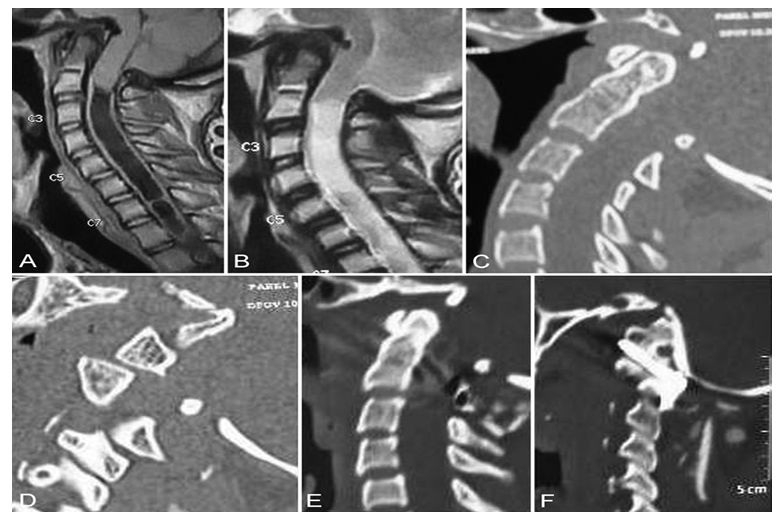

Functional MDCT in head flexion and extension enables identification of articular instabilities at the CCJ. Types of atlantoaxial dislocation on MDCT:• Type I — Anterior atlantoaxial dislocation: the articular surfaces of the atlas (C1) are shifted anteriorly relative to the axis (C2).• Type II — Posterior atlantoaxial dislocation: the articular surfaces of C1 are shifted posteriorly relative to C2.• Type III — Central atlantoaxial dislocation: no obvious joint displacement on standard or dynamic images. | Figure 2. Types of atlantoaxial dislocation on MDCT |